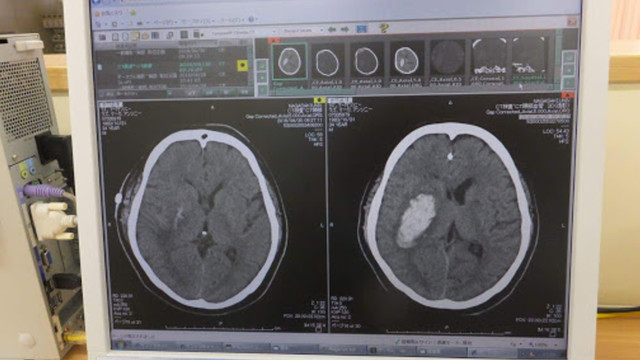

However, on 29 June 2018, Mark's fellow students were alerted to gibberish he was sending on the group's Messenger thread. After deciphering that he was trying to tell his friends that he thinks he had a stroke alone in his apartment, they immediately called emergency services and Mark was taken to the university hospital.

A ruptured aneurysm was what caused the left side of his body to be completely paralyzed. Unable to stop the bleeding, Mark was then scheduled for emergency surgery and underwent a major operation to stop the bleeding immediately.

Mark is now confined in the intensive care unit of Nagasaki University Hospital. The operation was a success and he is now slowly getting more responsive. However, the efforts to save his life are racking up bills for medication and rehabilitation.